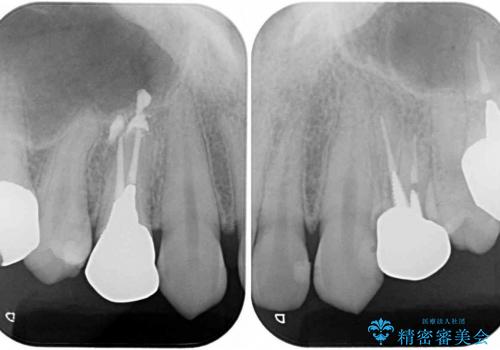

- 口を開けたときに目立つ銀歯を気にして来院された患者様です。

保険診療では銀歯となってしまうため、審美面の改善を目的として、オールセラミッククラウンにて補綴することとしました。

今回治療を行った小臼歯と呼ばれる歯は、保険診療ですと銀歯、またはプラスチックのクラウンとなってしまいます。プラスチックは装着したばかりは白いのですが、その後著しく変色をし、また強度も低いため、銀歯同様長期的に装着することはお勧めできません。

オールセラミッククラウンを装着したことで、審美性が改善されたことはもちろん、不適合な銀歯とは異なり、歯肉の腫れもきれいに引き、患者様には大変満足していただきました。